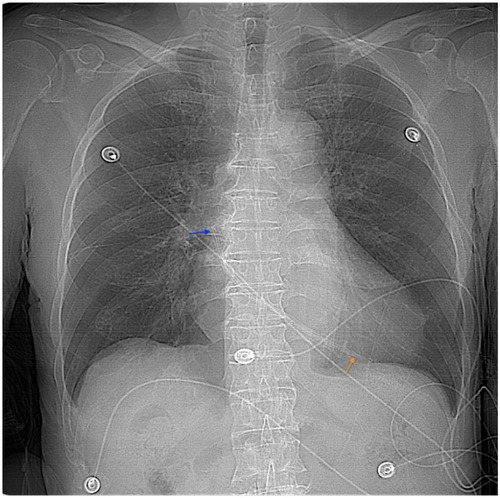

Background: With the advancements in endovascular techniques, reports of rare vascular complications have increased. This case describes the accidental fracture of a non-cuffed hemodialysis catheter and its subsequent endovascular management, offering valuable insights for the treatment of similar intravascular foreign bodies (IFBs). Case Report: An 83-year-old male with a non-cuffed catheter presented after a catheter fracture. Radiographic imaging confirmed migration of the fragment to the right atrium. After a multispecialistic collaboration assessment, endovascular retrieval was performed via right femoral access using a filter retrieval device under fluoroscopic guidance. The catheter fragment was successfully captured and removed without procedural complications. The patient recovered uneventfully and remained well at follow-up evaluations. Conclusion: This case highlights the efficacy and safety of percutaneous endovascular retrieval for managing IFBs, providing a minimally invasive alternative to surgery with high success rates. Meticulous catheter handling and regular integrity assessments are critical to prevent and promptly manage such events.